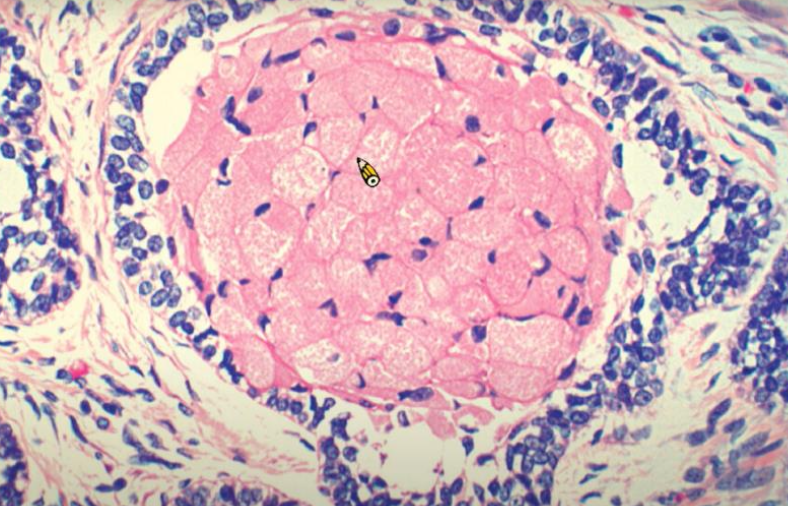

follicular Pattern

• 最常見

alt text